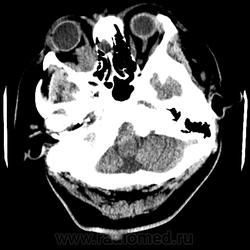

Женщина 48 лет, поступила с подозрением не ОНМК. На КТ -данных за ОНМК не обнаружено, но в правой орбите ретробульбарно мягкотканное образование +45HU, признаков деструкции и ремоделирования костных структур орбиты не наблюдается, медиальная и нижняя прямая мышца отчетливо не дифференцируются, зрительный нерв тесно прилежит к данному образованию. После КУ гомогенное накопление КВ и повышение плотности до +65HU. Экзофтальм. Жалобы на снижение зрения. Год назад делала МРТ ГМ, на снимке патологии орбит не увидел. Идиопатическая псевдоопухоль орбиты?

В мягких тканях носогубного треугольника справа тоже образование.

Натив

Контраст

На первое место все же поставила бы гемангиому. Локализация, возраст, пол, флеболит, случайная находка, безболезненный экзофтальм, ремоделирование стенок орбиты -это за гемангиому.

Кавернозная гемангиома? Ремоделирования стенок орбиты как раз таки нет, они интактны. Должна быть псевдокапсула, а здесь больше похоже на инфильтрацию прямых мышц, я за псевдоопухоль.